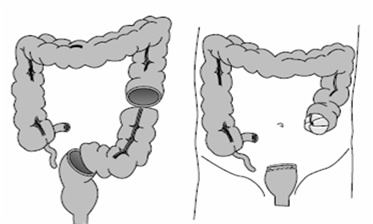

Μετά από επείγουσα σιγμοειδεκτομή, κολο-ορθική αναστόμωση είναι εφικτή ανάλογα με την κατάσταση του ασθενούς (αιμοδυναμική σταθερότητα, ελεγχόμενη σήψη, απουσία κοπρανώδους περιτονίτιδας). Ακόνη και σήμερα, ωστόσο, η παραδοσιακή επέμβαση κατά Hartmann προτιμάται από πολλούς. Περιλαμβάνει σιγμοειδεκτομή, τελική κολοστομία κατιόντος κόλου και σύγκλειση του ορθικού κολοβώματος (Εικόνες 5, 6). Η αποκατάσταση της συνέχειας της πεπτικής οδού με αναστόμωση μεταξύ του κατιόντος κόλου με το ορθό λαμβάνει χώρα 6 μήνες αργότερα.

Εικόνα 5.

Επέμβαση κατά Hartmann